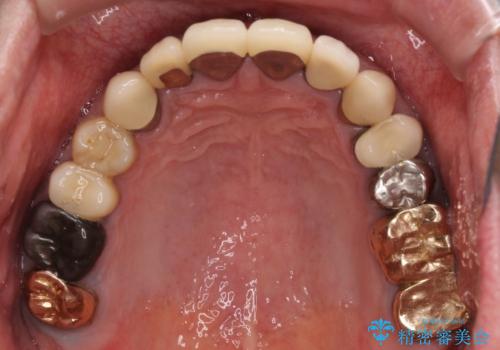

- 抜歯した歯や抜歯が必要と思われる歯を放置したため、奥歯に不快を感じているとのことで来院された患者様です。

右下は奥歯が抜歯したスペースを塞いでしまい、左下はブリッジの支台歯の1つが破折している状態でした。

また、下顎前歯にはスペースがあり、コンポジットレジンでスペースを閉じている状態だったので、前歯のスペースを解消しつつ、奥歯にスペースを獲得するよう矯正治療を行うこととしました。

並行して左下にはインプラントを埋入し、上顎臼歯部の気になる部分も根管治療などを進めて行き、矯正治療を終えると同時に補綴治療を行うこととしました。